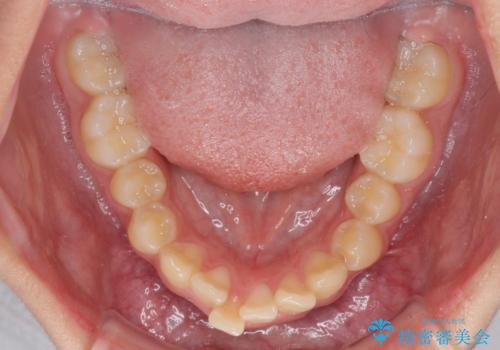

下の前歯が隠れてしまうほど深い咬み合わせ 高校生のインビザライン矯正治療

- 前歯の叢生と深い咬み合わせを気にして来院された患者様です。

奥歯の咬み合わせを見ると、上顎が下顎に対して相対的に前方にありました。

深い咬み合わせを改善するためには、上顎臼歯を後方に移動させつつ、下顎の小臼歯を直立させる必要があります。